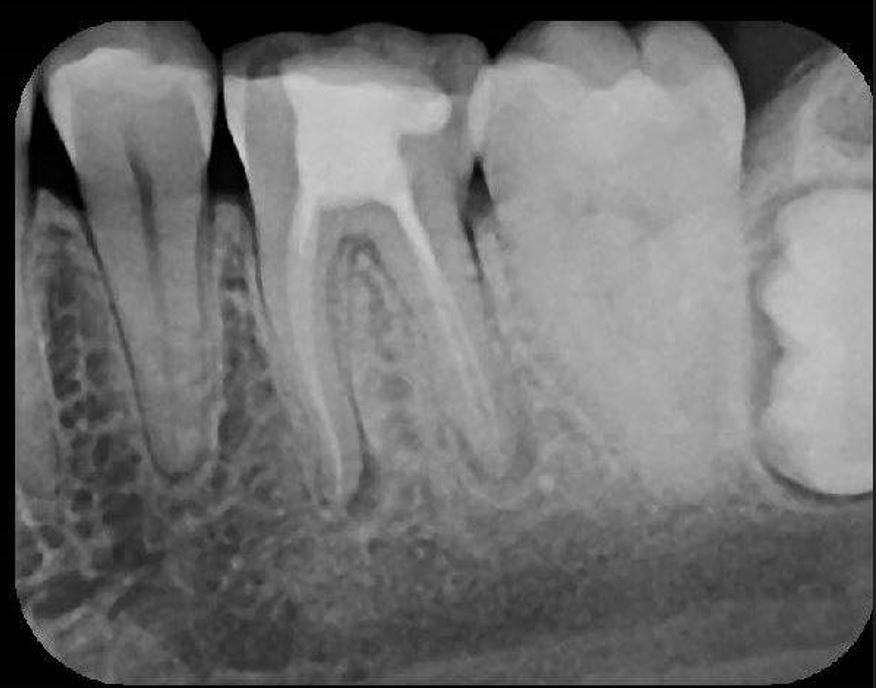

X-Ray 1: How many caries are present?

(Required)

X-Ray 1: How many PAP's are present?